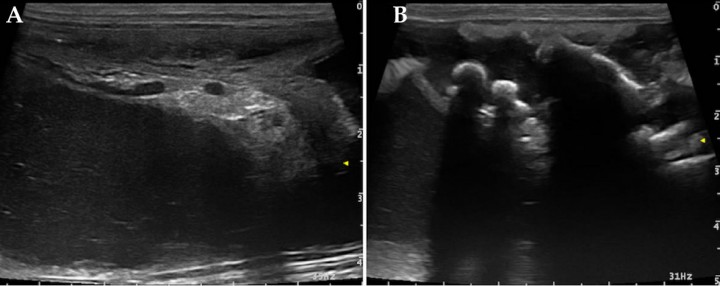

En este caso se realizó una ecografía abdominal en la que se observó el útero distendido con contenido hipoecoico con marcada celularidad (Fig. 3A). No se visualizaron fetos formados, aunque en el interior del útero se observaron estructuras hiperecogénicas que generaban sombra acústica, compatibles con restos óseos (Fig. 3B). Al seguir el recorrido del cuerno uterino izquierdo se apreció signo de remolino (whirlpool sign) que involucraba la vascularización uterina, indicativo de torsión (Vídeo 1). El Doppler color ayudó a la visualización de este patrón en espiral al resaltar el flujo sanguíneo de los vasos implicados, comprobándose posteriormente en la cirugía (Fig. 4).

<div class=\"Basic-Text-Frame\">

<p>Imágenes ecográficas. (<strong>A</strong>) Se observa contenido uterino hipoecoico con marcada celularidad. (<strong>B</strong>) Se observan estructuras hiperecogénicas que generan sombra acústica compatibles con restos óseos intrauterinos.</p>

Figura 3

Imágenes ecográficas. (A) Se observa contenido uterino hipoecoico con marcada celularidad. (B) Se observan estructuras hiperecogénicas que generan sombra acústica compatibles con restos óseos intrauterinos.